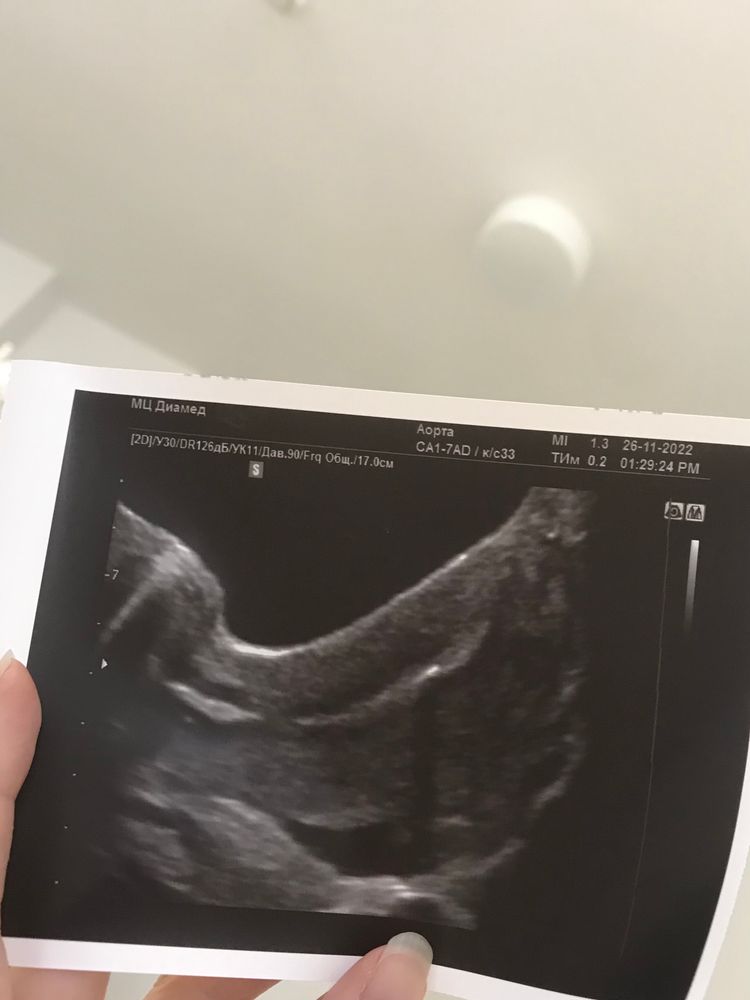

Затем из соседнего окошечка доносится фраза «Все чисто». Мне передают в руки фотку с блестящей звездочкой.

На сей раз я знаю, что эта звездочка не мой эмбрион, а всего лишь навсего капелька жидкости в которой он плавает. Но это знание нисколечко не уменьшает значимость момента.

Я спокойно дошла до палаты, удобно устроилась на кровати, конечно же сфотала и отправила снимок УЗИ супругу. Как и было велено, через время я сходила в туалет и вставила Утрожестан. И я снова боялась «выписать» эмбрион. Хотя и знала, что подобного просто не может произойти. Это словно зажать песчинку в руке, так же и с маткой. Но этот глупый страх все равно был со мной.